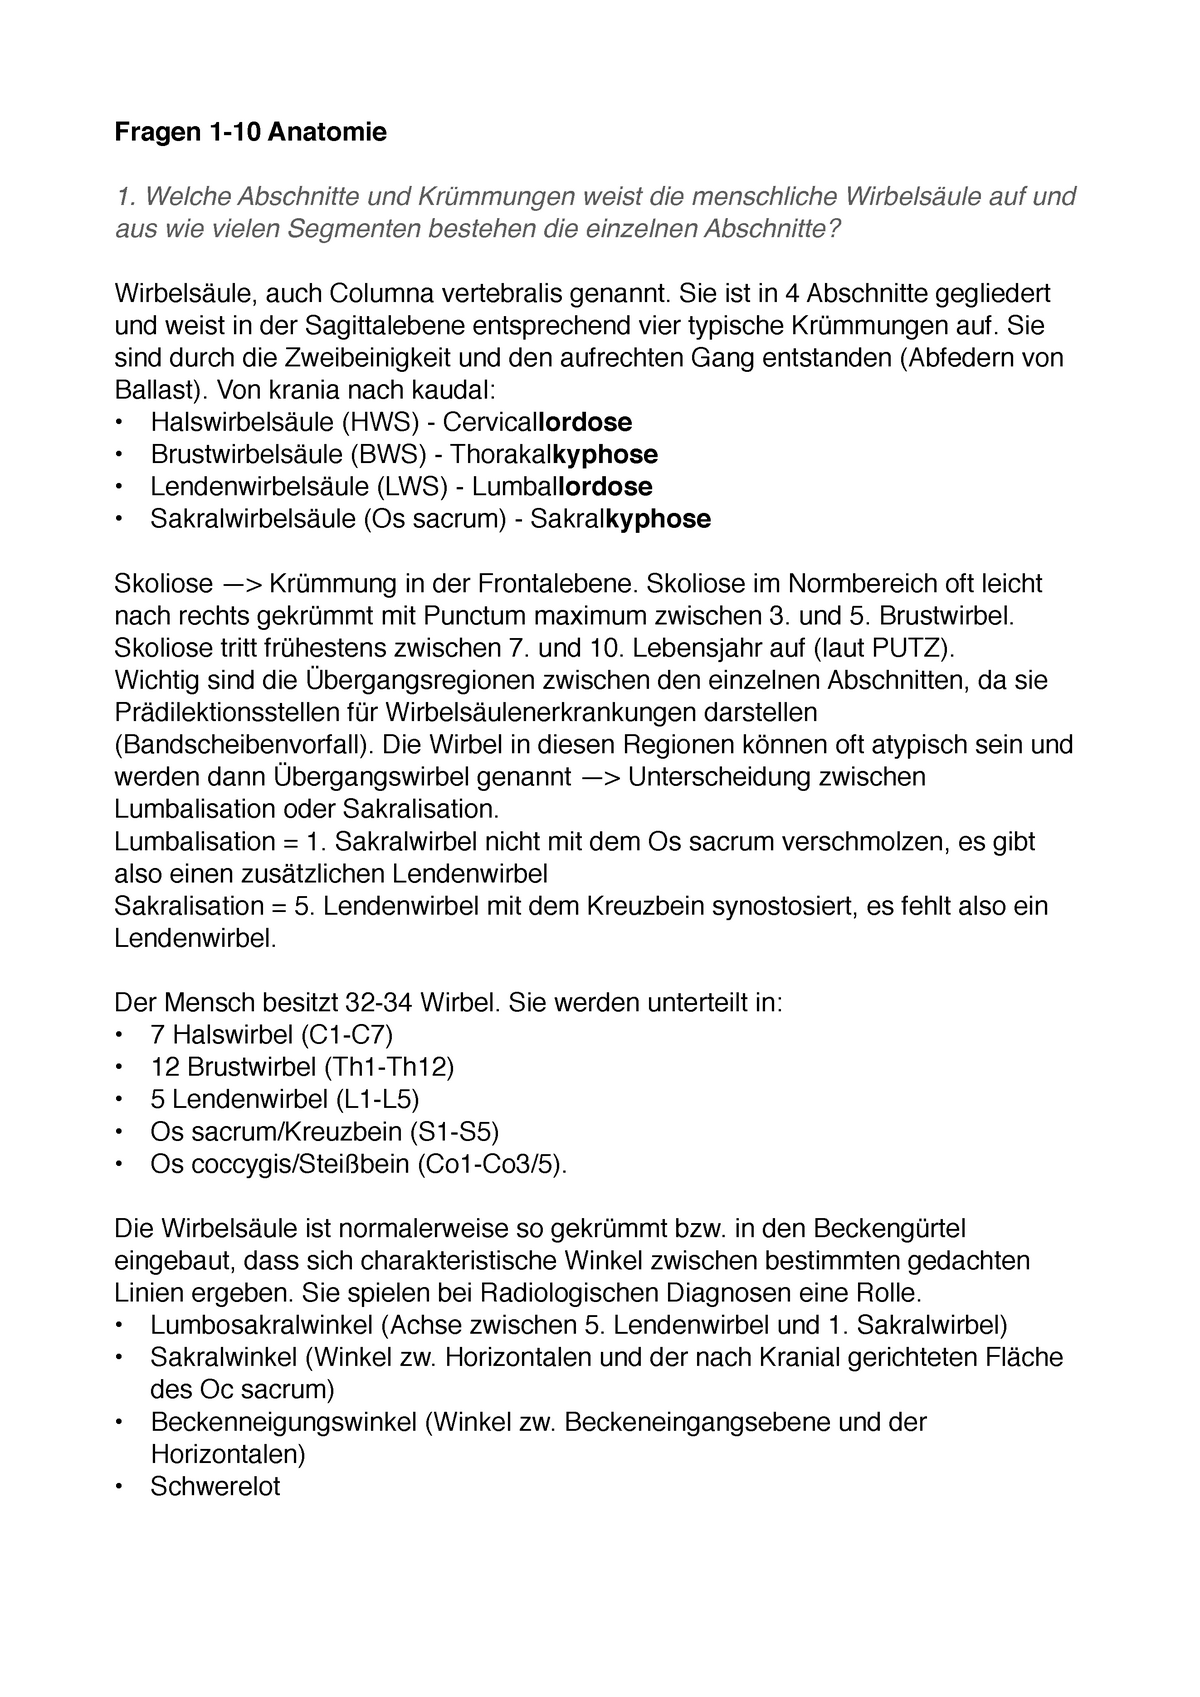

2025 07 10

Https www alamy de die cambridge natural history zoologie wirbelsaule 283 der centra oder einrichtungen der wirbel werden durch die paare von iuterventralia gebildet wahrend der basiventralia reduziert werden fort abb 56 zusammensetzung der wirbel der reptilien der von dem ersten und zweiten halswirbel dargestellt 1 atlas hws und achse zweite wirbel der kroko dilus 2 atlas und achse des metriorhynchus jurassic krokodil 3 analyse der ersten beiden halswirbel eines krokodils 2 zweite basiventral komplexe oder intercentrum fuhr nach oben in den meniskus oder interver image232173708 html (Dateityp jpg)

Die Cambridge Natural History Zoologie Wirbelsaule 283 Der Centra Oder Einrichtungen Der Wirbel Werden Durch Die Paare Von Iuterventralia Gebildet Wahrend Der Basiventralia Reduziert Werden Fort Abb 56 Zusammensetzung Der

Https www alamy de bulletin der naturlichen histort museum geologie serie s andrews und y fernandez jalvo abb 16 a menschliche achse wirbel m 54042 zeigt die konformation des cut markierungen entlang der vorderen oberflache dies ist der bereich der befestigung der vorderen langsband und daruber hinaus die superior markierungen sind wahrscheinlich auf die ablosung der achse von der atlas und die hinteren markierungen aus um die loslosung der achse von der dritten halswirbel x 12 b schematische zeichnung des menschlichen schadel und oberen wirbel angezeigt um die disposition der beiden muskeln die an der inneren oberflache o image233869895 html (Dateityp jpg)

Bulletin Der Naturlichen Histort Museum Geologie Serie S Andrews Und Y Fernandez Jalvo Abb 16 A Menschliche Achse Wirbel M 54042 Zeigt Die Konformation Des Cut Markierungen Entlang Der Vorderen Oberflache

Https www alamy de die katze eine einfuhrung in das studium der backboned tiere vor allem saugetiere katzen anatomie vergleichende 42 die katze chap iiiahneln die funfte zervikalen die siebte jedoch hat eine langere dornfortsatze prozess wie von einem brustwirbel und nur keine wirbelsaule ganal dass ein teil der transversalen prozess entwickelt werden die mit root uber dem wirbelkanal und mit der ein apophysis prozess der transversalen prozess des funften wirbel entspricht diese teile daher konnen getroffen werden zu vertreten abb 20 die achse wirbel a in der seitenansicht b in der vorderansicht c zuruck image235092628 html (Dateityp jpg)

Die Katze Eine Einfuhrung In Das Studium Der Backboned Tiere Vor Allem Saugetiere Katzen Anatomie Vergleichende 42 Die Katze Chap Iii Ahneln Die Funfte Zervikalen Die Siebte Jedoch Hat Eine Langere Dornfortsatze

Bilder können urheberrechtlich geschützt sein Mehr Informationen

:background_color(FFFFFF):format(jpeg)/images/article/de/wirbelsaule/a1wjCWbEAeBhCqqodBbjHQ_Wirbels_ule_von_dorsal.png)